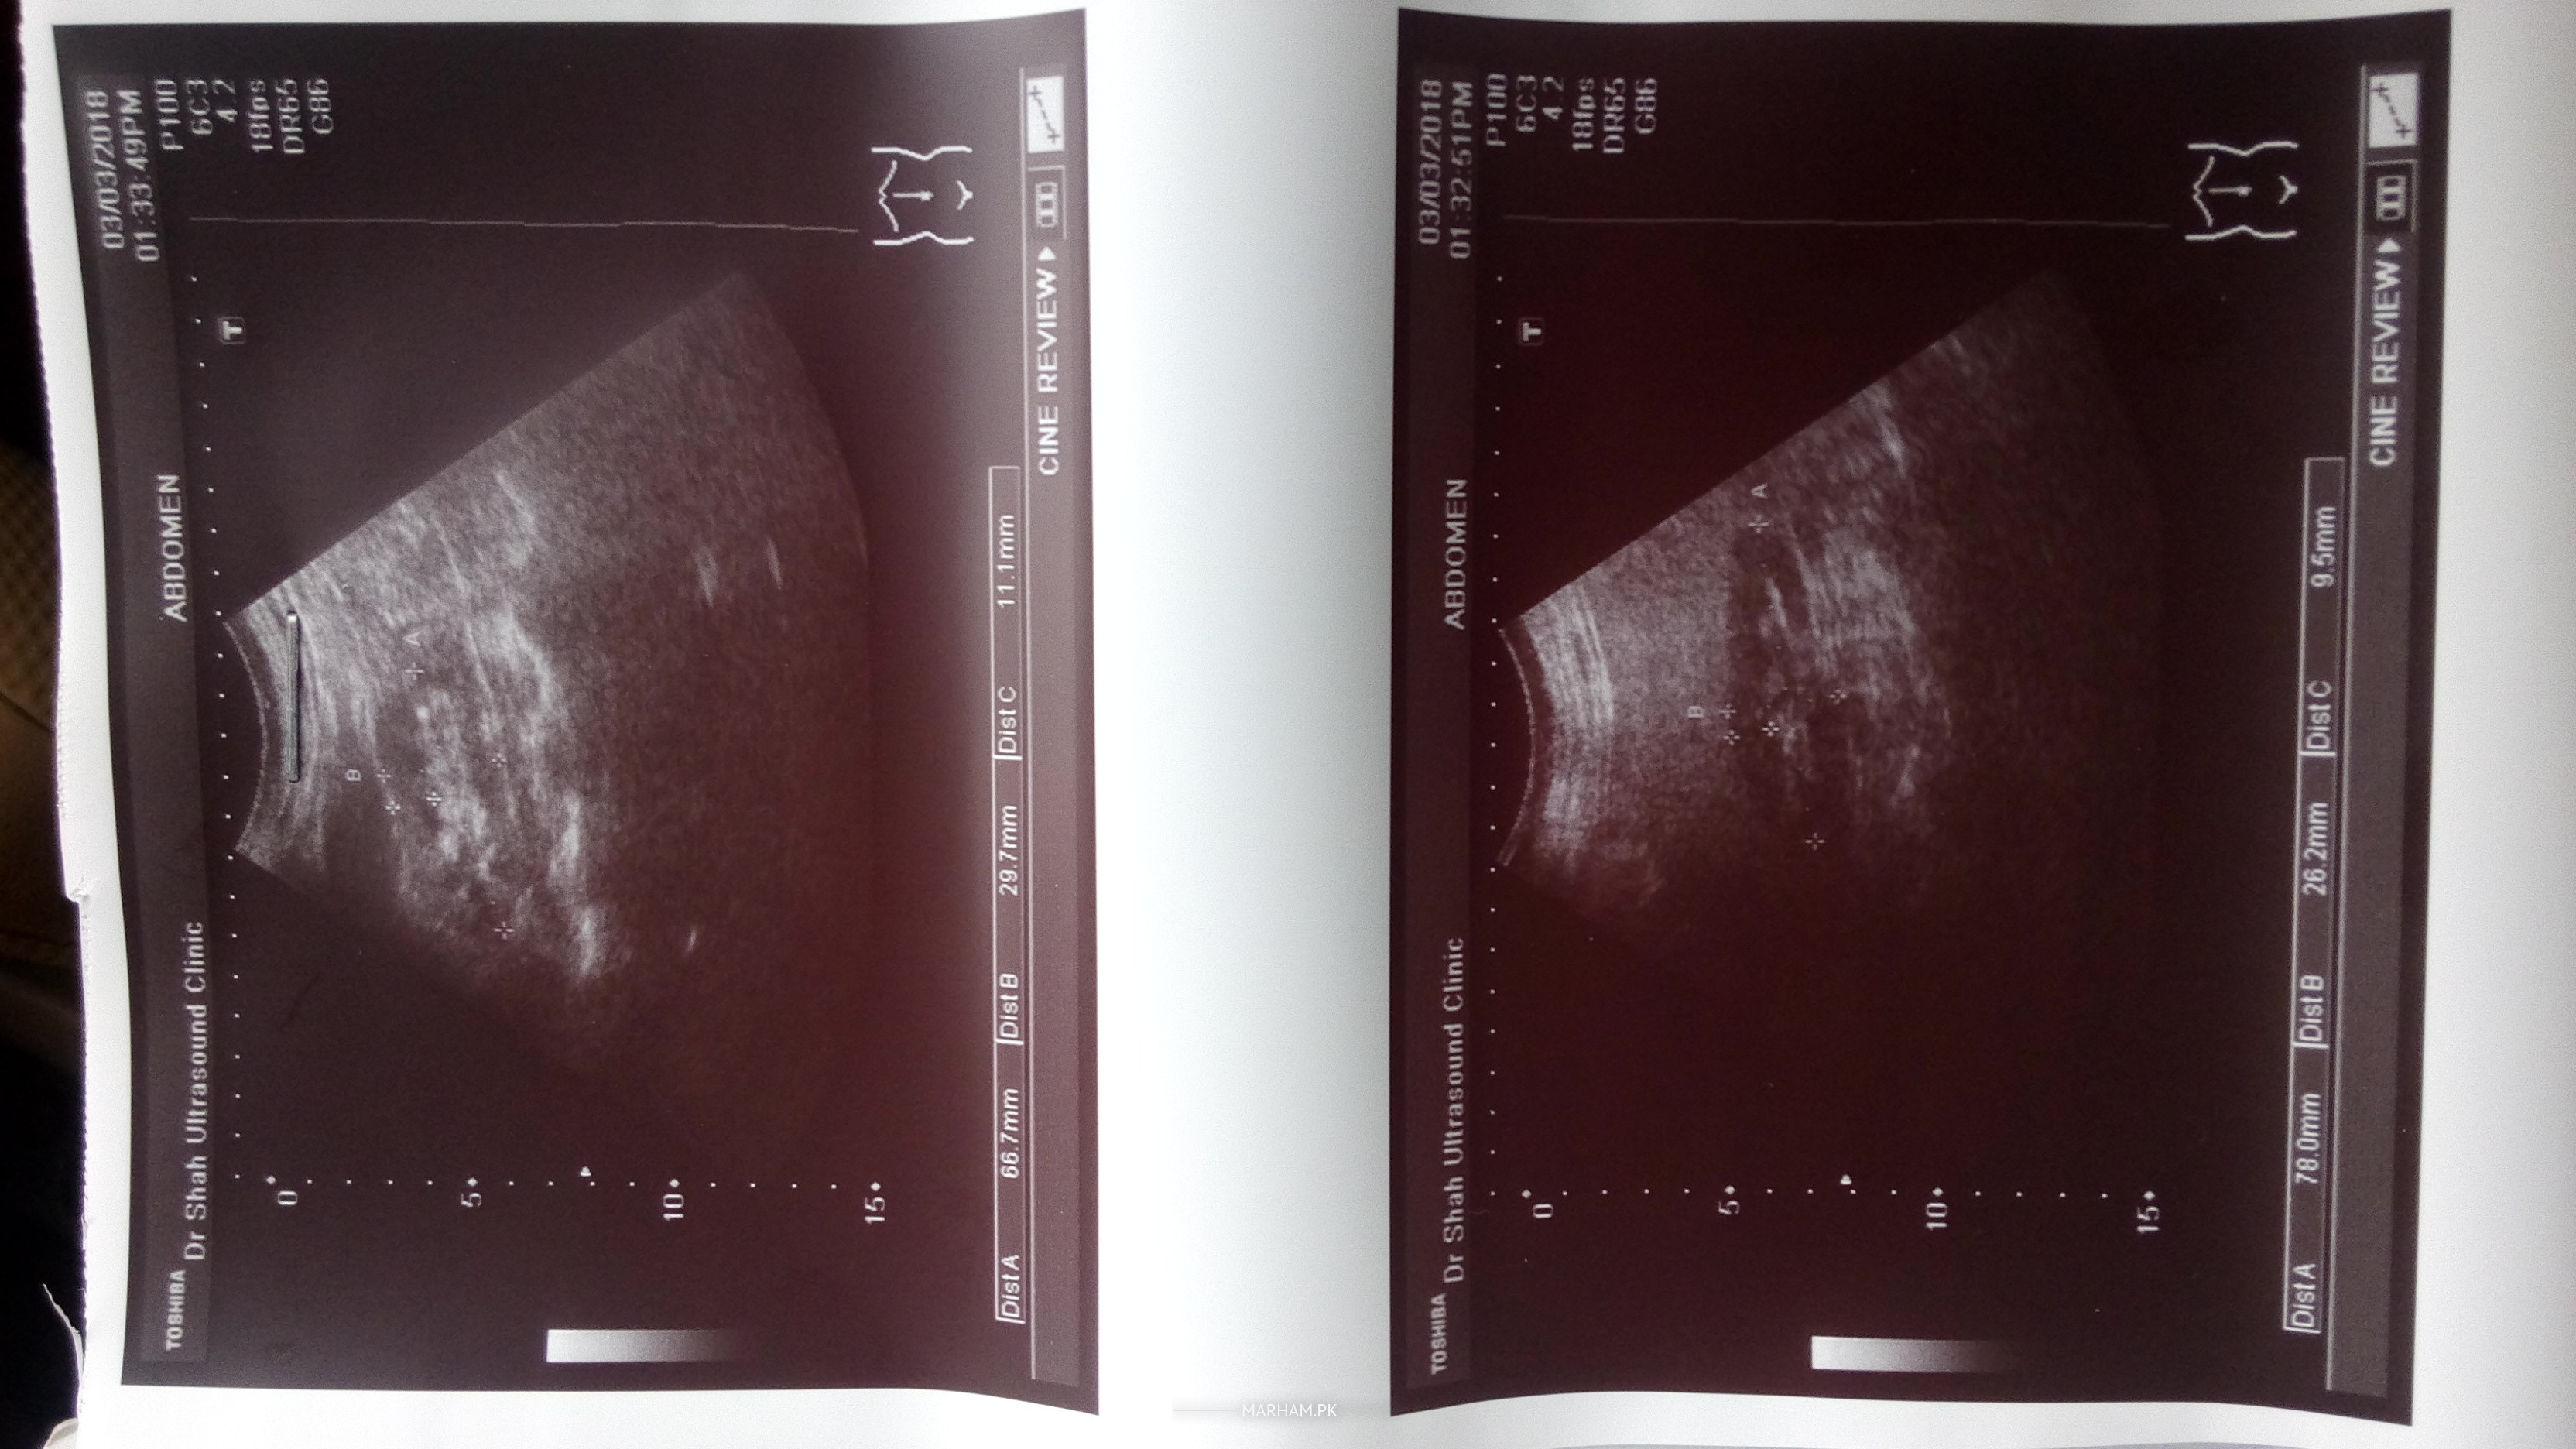

Doctors especially nephrologist . please see this ultrasound are the kidneys?about size and shape?(Rt.78x26.2x9.5mm).(left.66.7x29.7x11.1mm) size is in some one tell me?